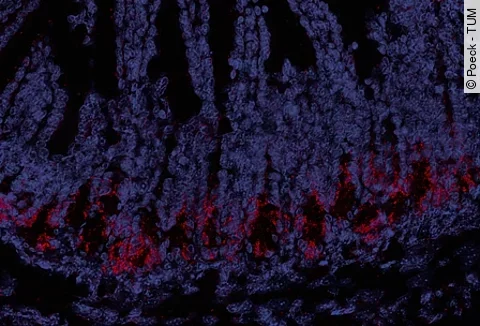

Schnittbild eines Epithels